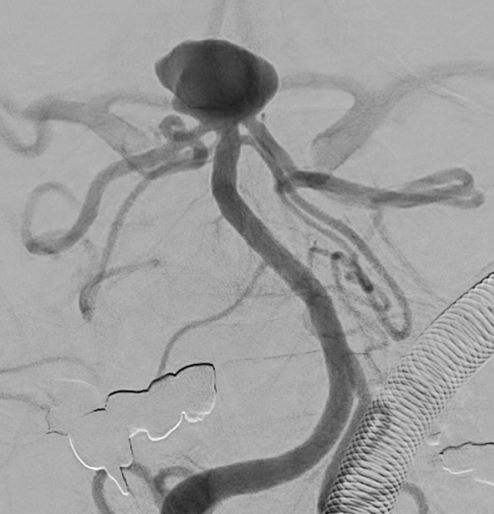

Apoplexy 14

【脳動脈瘤;矢印の部位】

治療の方法は、開頭して動脈瘤にクリップをかけるクリッピングという方法と、コイル塞栓術といって頭を開けないでカテーテルで治療する方法があります。どちらの手段にも有利な点と不利な点があり、当院では動脈瘤の場所、形状、患者さんの状態などに応じて両者を使い分けています。